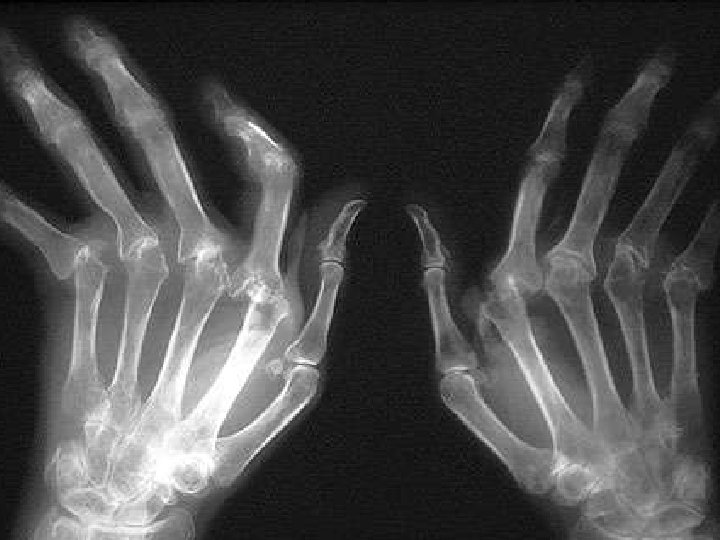

Patterns of radiographic changes RA gout OA

Patterns of radiographic changes psoriasis RA OA gout CPPD http: //www. gentili. net/Hand/summary. htm

Progression of RA erosions How fast is joint damage progressing? A. Soft-tissue swelling, osteopenia, no erosions A B C B. Thinning of cortex with minimal joint space narrowing C. Marginal erosion with joint space narrowing ACR Clinical Slide Collection, 1997.